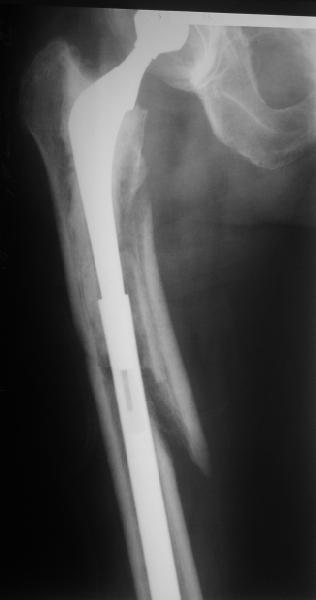

Спасибо за обсуждение. После нескольких дней тракции аппаратом сделали. Попытка закрытой репозиции не удалась из-за смещения по ширине, мешали фрагменты цемента. После их удаления репозиция получилась. Еще убрали немного цемента с ножки по латерльной стороне, чтобы обнажить 40-50 мм ее дистальной части, для плотной посадки гвоздя. Дальнейшее введение гвоздя было несложным. Протез показался нам стабильным в проксимальной части как латерально, так и медиально. Картинки в приложении.

THX for the discussion. After few days of traction by ex-fix the surgery was performed. An attempt of closed nailing was unsuccesful because of fragment translation, which was blocked by cement fragments. After removal of broken cement pieces reduction was reached "automagically". Also some cement from lateral part was removed by

chisel to expose distal 40-50 mm of the stem to allow tight fit of the nail. Further fixation by the nail was pretty easy and straightforward. Images attached. The stem looked stable in its proximal part both laterally and medially. Comments/critics are welcome.